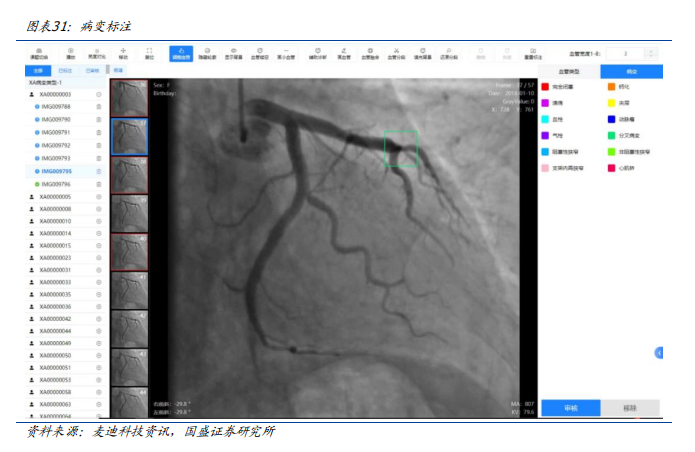

早在2023年,由麦迪科技研发的心血管医学影像人工智能科研平台在复旦大学附属中山医院落地。该项目是基于复旦大学附属中山医院在心血管疾病方向的学科集群优势,研发的一款与影像大数据库连接的“一站式”心血管医学影像人工智能科研平台,实现科研影像数据的快速收集,以及人工智能科研所需的标注、清洗、存储、训练和验证等功能。

心血管医学影像人工智能科研平台是基于计算机视觉网络模型的人工智能技术框架作为AI基础服务层,打造心血管人工智能影像分析平台为临床提供辅助诊疗服务。包含冠脉造影、血管内超声及CT血管造影等心血管疾病影像检测智能分析功能。通过对冠脉造影血管轮廓智能提取可以快速定位血管狭窄,完成血管狭窄分析,实现狭窄血管重建与定量测算,分析计算狭窄的功能学指标参数;同时还提供手术支架建议,便于快速制定介入手术方案。通过血管内超声影像分析可以快速完成血管内超声图像分析,实现斑块定位与测算,便于快速制定后续的治疗方案。